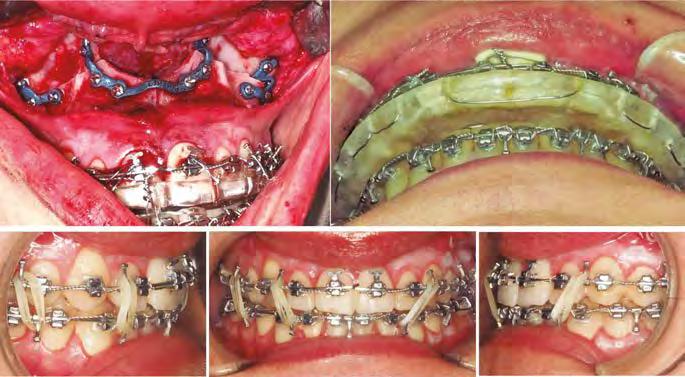

–Corticotomías y Ortodoncia. Ampliando límites del movimiento dental, por la Dra. Aranzazu Senosiain y cols. [50]

–Tratamiento de un caso de Ortodoncia y Cirugía Ortognática con placas preformadas y tecnología 3D, por la Dra. Elena Bonilla Morente y cols. [62]

–Uso del anclaje esqueletal como alternativa eficiente en el manejo ortopédico de clases III por deficiencia de maxilar superior, por el Dr. Carlos Becerra y cols. [74]

–MARPE, una alternativa a la disyunción en el paciente adulto, por el Dr. Enrique Solano y cols. [88]